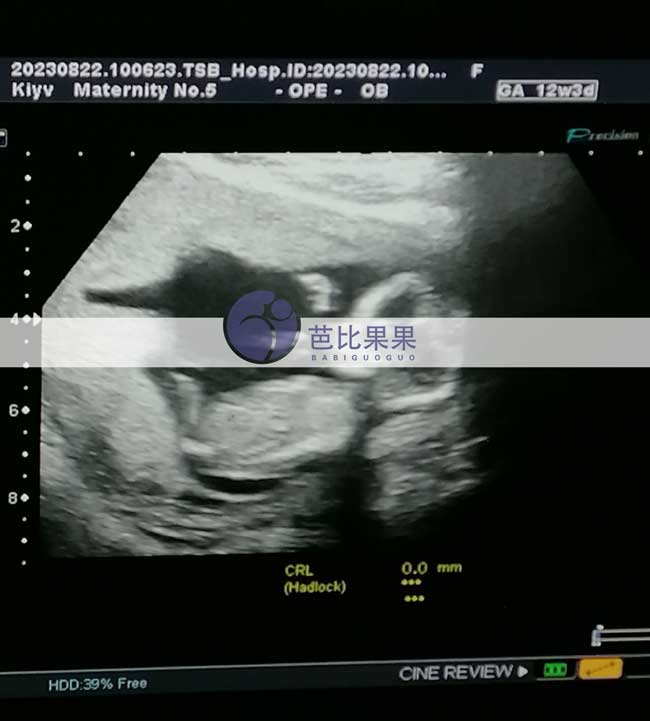

C先生夫妻孕12周的乌克兰试管妈妈做B超

C先生夫妻的乌克兰试管妈妈来做B超啦,已经孕12周,宝宝发育的很好,要一直顺顺利利哦